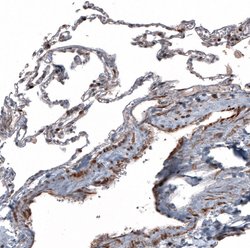

The basic helix-loop-helix transcription factor TCF21/Pod1 (also called capsulin or epicardin) is involved in kidney, lung and spleen organogenesis. It is also essential for normal development of the testes and ovaries. TCF21/Pod1 is involved in the transcriptional repression of steroidogenic factor 1 (Sf1/Nr5a1/Ad4BP), an orphan nuclear receptor that regulates the expression of multiple genes (including Scc) that mediate sexual differentiation.

| Immunohistochemistry, Western Blot | |